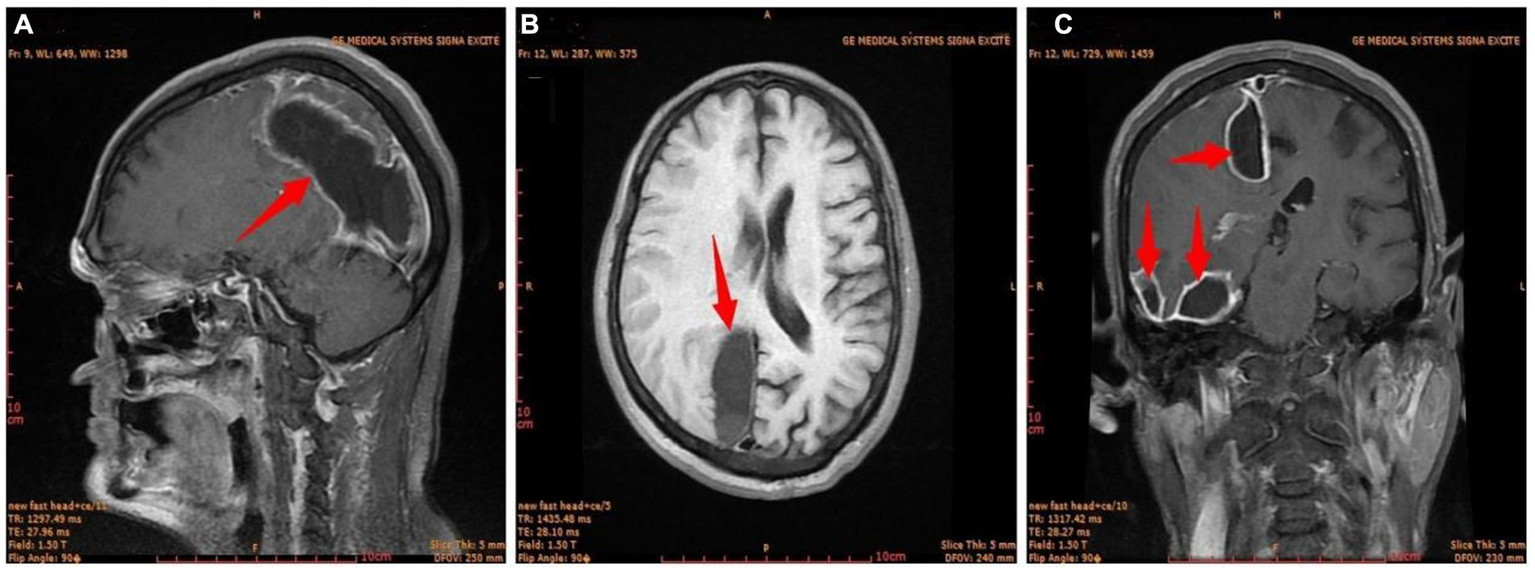

The condition of the right eye steadily improved 6 h after the first surgery. Multiple brain abscesses were discovered during postoperative MR examination (Figure 3). On the 3rd postoperative day, the intracranial abscess was punctured and drained under monitored anesthesia care (MAC). Blood and pus samples were subjected to a drug sensitivity test and bacterial culture, respectively. Postoperative recovery went well. After the second surgery, the motor function and muscle strength of the left upper and lower limbs gradually improved. There were no signs of widespread infection. He was discharged from the hospital on April 11 after a CT scan showed no abnormalities (Figure 4).

Figure 3

The first postoperative craniocerebral MR image. (A) Sagittal; (B) transverse; (C) coronal. Red arrow, brain abscess.